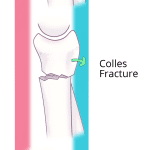

- Acute, comminuted, impacted, intraarticular distal radial fracture with 1.5 cm volar displacement and comminution of the distal articular surface

- Likely extension into the distal radioulnar joint

- Acute ulnar styloid fracture with mild radial displacement

- Acquired ulnar positive variance

- Smith fracture (Frykman VIII)

Acute, comminuted, impacted, intraarticular distal radial fracture with 1.5 cm volar displacement and comminution of the distal articular surface. Likely extension into the distal radioulnar joint. The distal radial fracture fragment maintains its articulation with the carpus.

Acute ulnar styloid fracture with mild radial displacement.

Acquired ulnar positive variance.